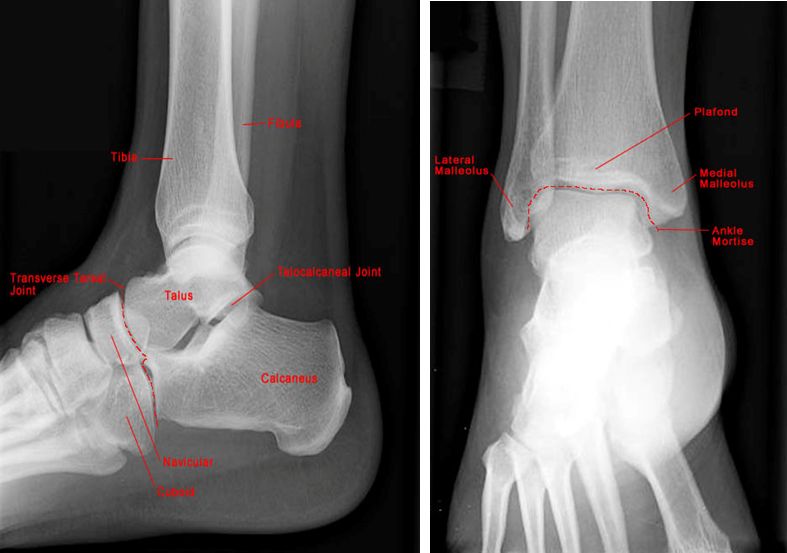

正常踝关节

踝关节骨折

三踝骨折

踝关节脱位

正常足侧位片